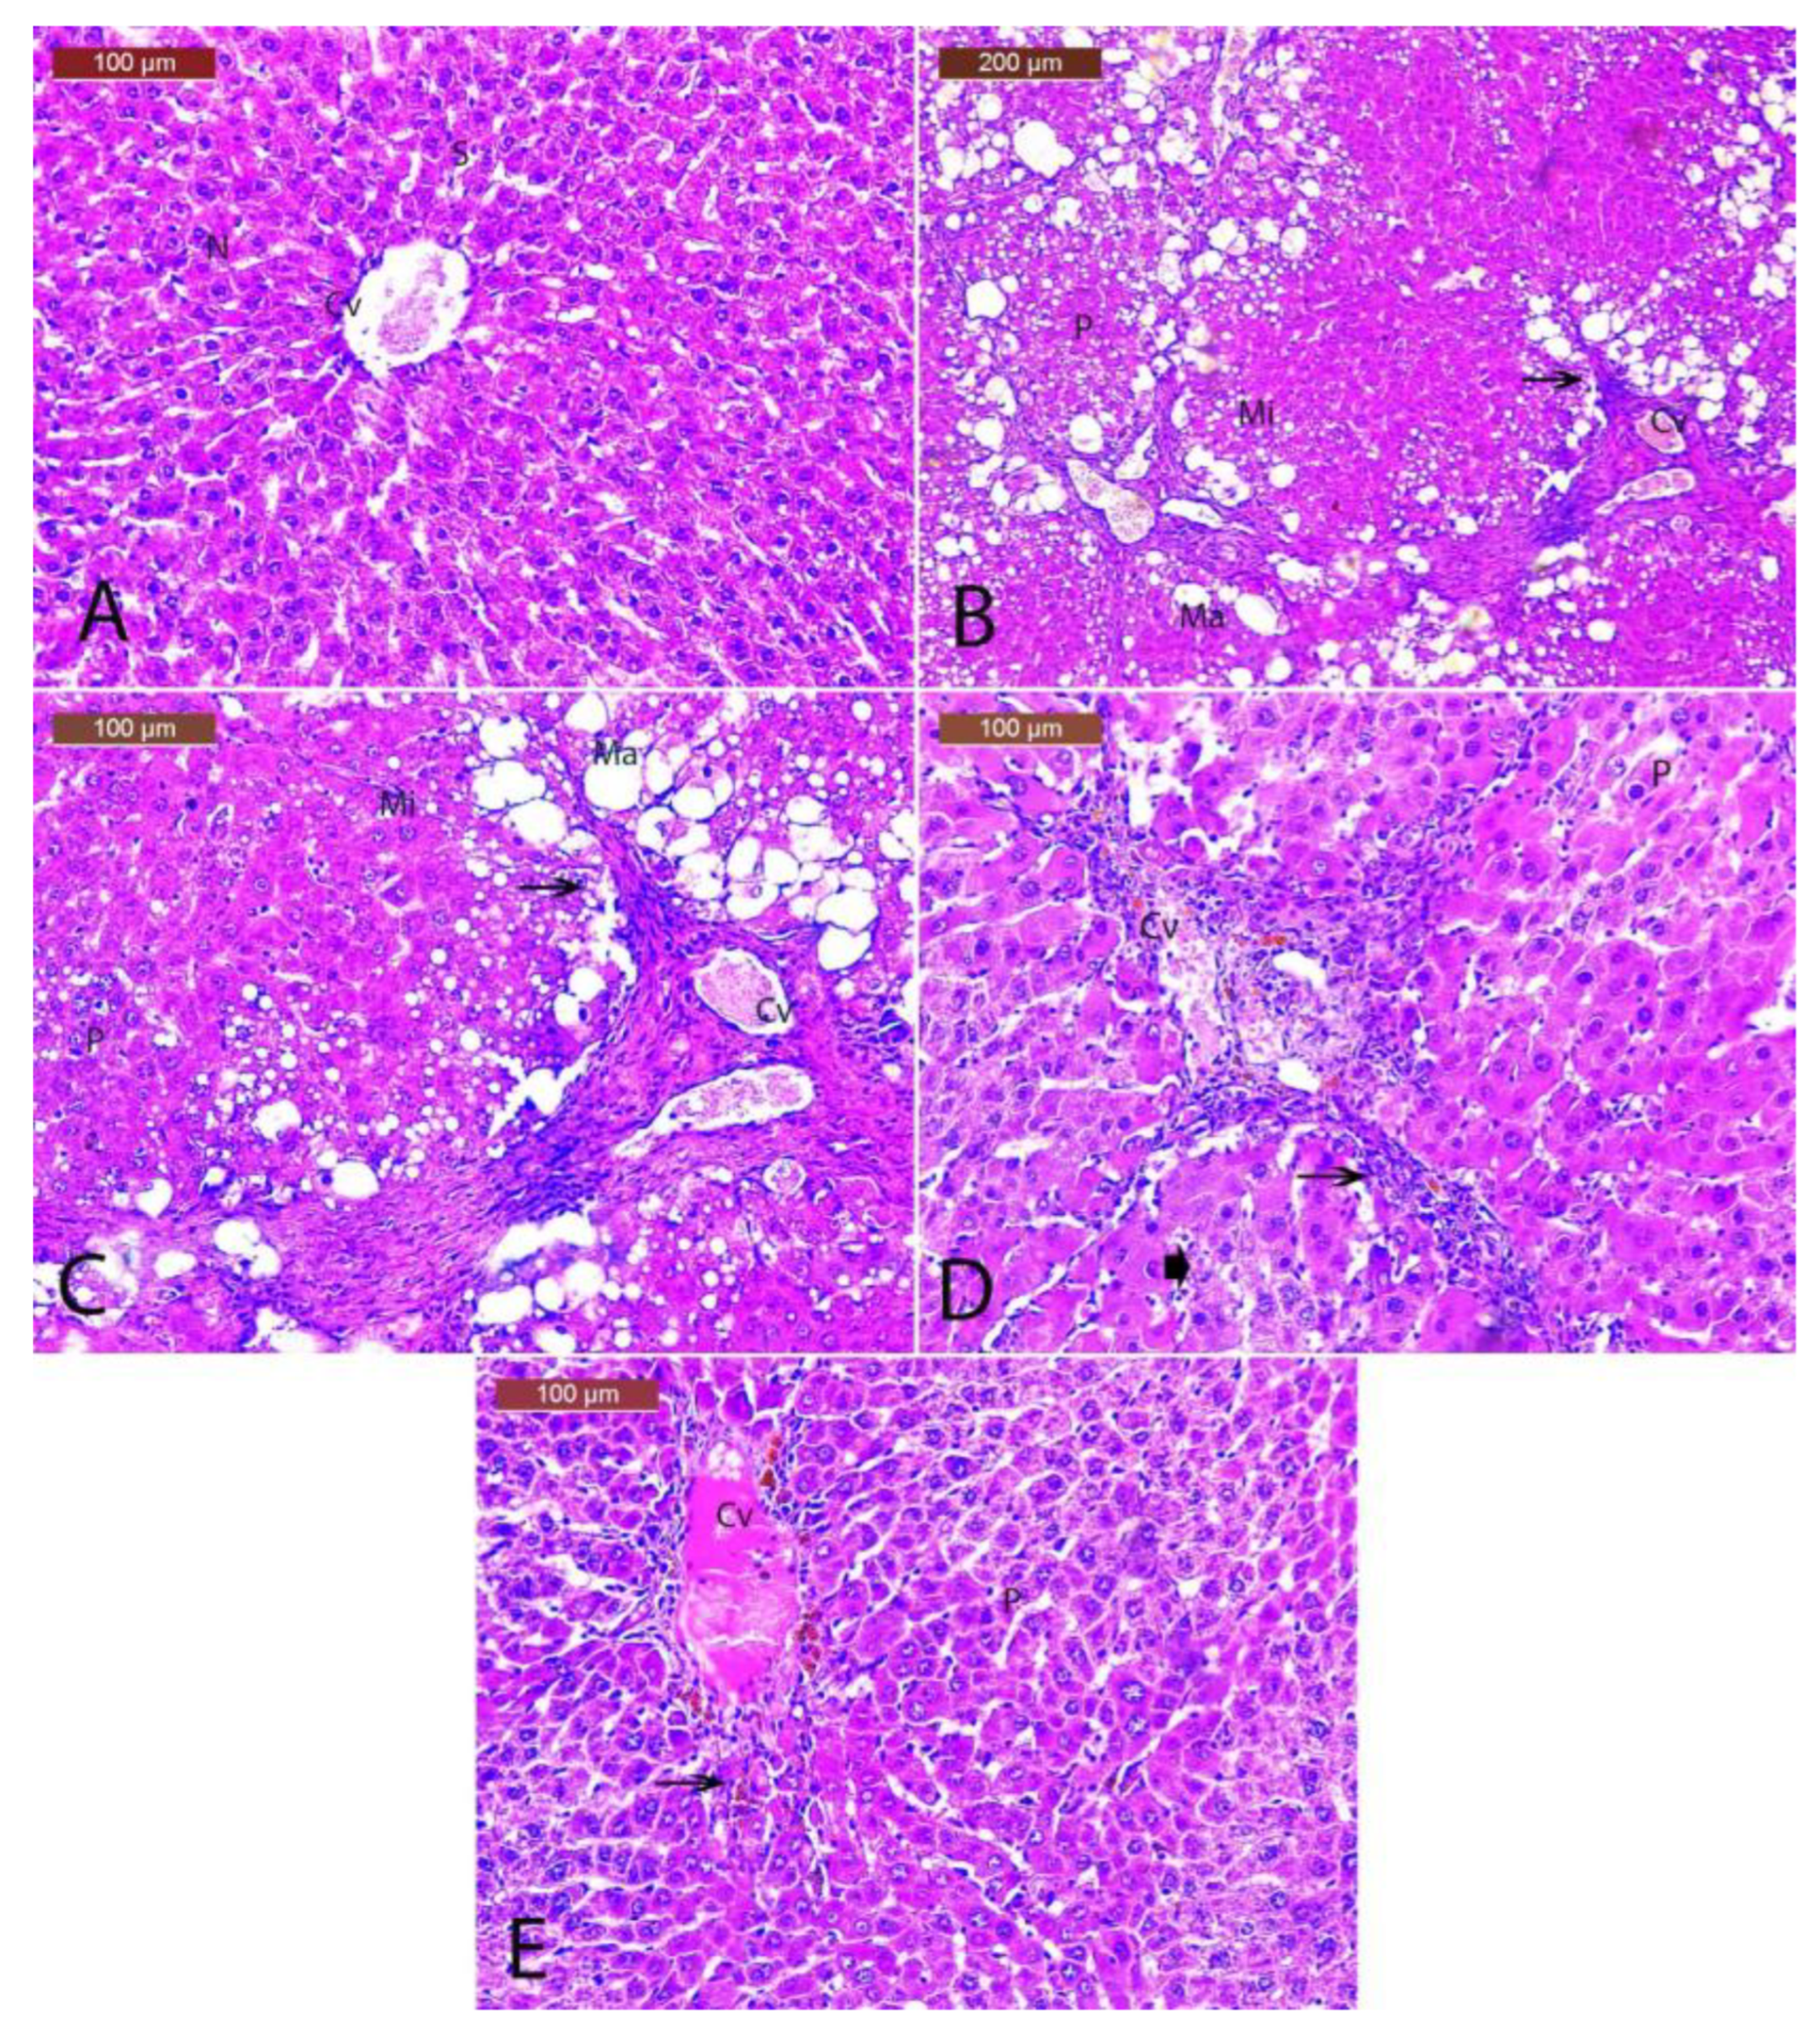

3.10. Histopathology of the Hepatic Tissues